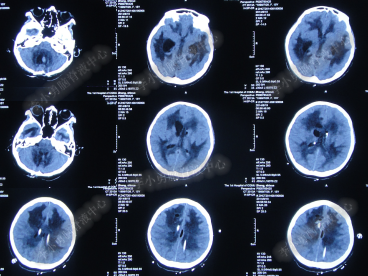

2014年8月31日住入李小勇脑脊液中心,入院时:卧床,表情淡漠,神志嗜睡;体温高37.9°C;头颅枕后正中手术瘢痕,结痂尚未脱落;左枕侧脑室外引流固定在位,尚通畅,可见淡红色浑浊脑脊液引出;颈抵抗,双肺呼吸音粗(图-27);头部CT检查示(小脑肿瘤术后颅内感染病例)脑室系统粘连严重伴双侧颞角脑室扩张明显,双侧侧脑室见引流管影,脑内见多发斑片低密度,中线结构无移位,颅骨术后改变(图-28)。

图-27:2014年8月31日入院时

图-28:2014年8月31日头部CT

入院第4天即2014年9月3日,左枕脑室外引流管引流脑脊液量不多,晨起4:00左右出现血压升高伴瞳孔扩大,4.5:2.0;多参数生理:心率102次/分,呼吸11次/分,血压141/96mmHg,血氧饱和度98%;急行头部CT检查示双侧侧脑室扩大,颞角扩张显著,双侧侧脑室见引流管影,位置变化不大,脑内见多发斑片低密度(图-29)。

图-29:2014年9月3日4点50分头部CT